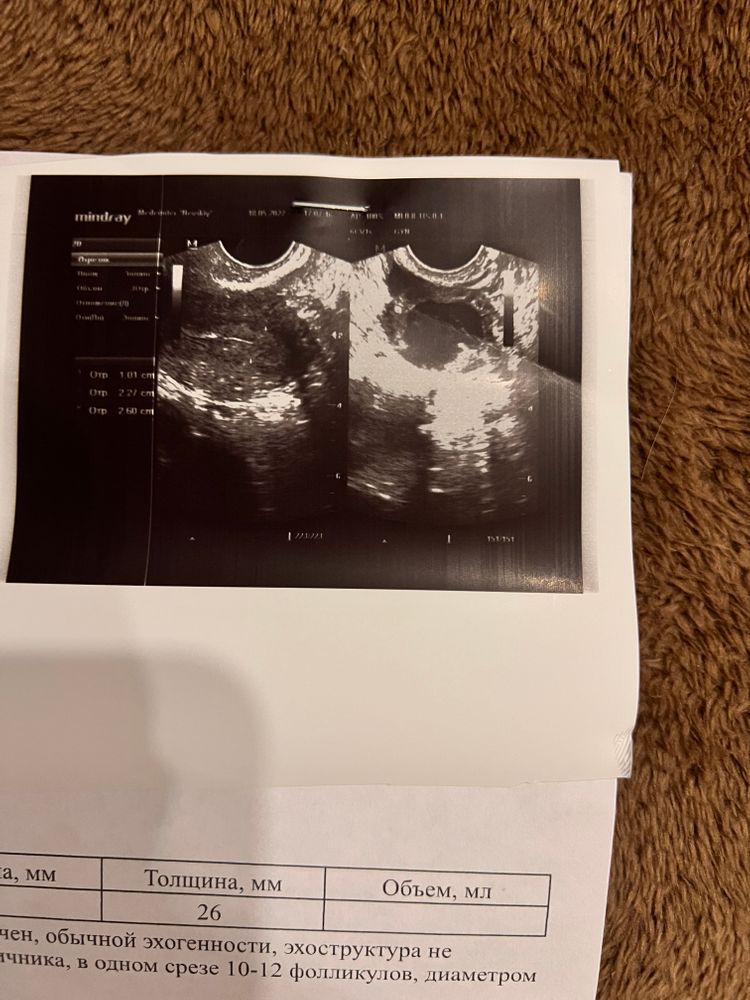

Результаты ТТГ Прогестерон после овуляции. Нормально ли?